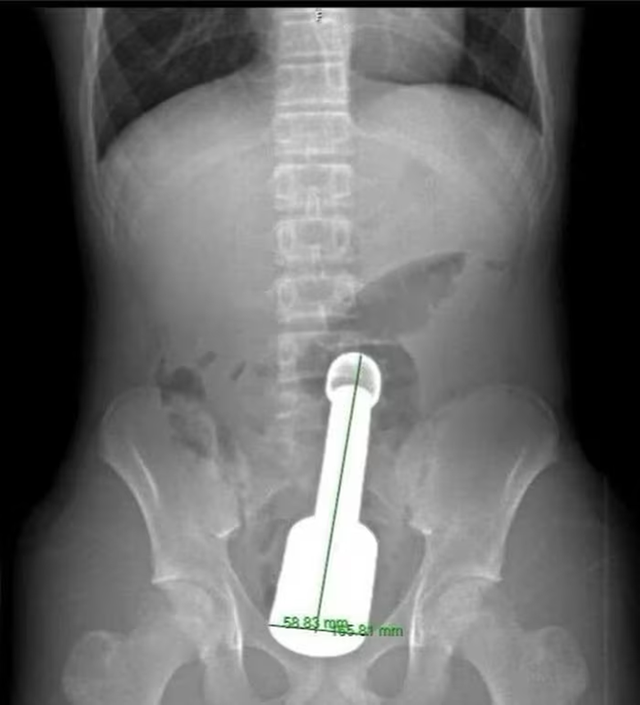

Hình ảnh chụp X-quang và dị vật được lấy ra khỏi hậu môn của bệnh nhân - Ảnh: BVCC

Theo các bác sĩ, dị vật được xác định là một chiếc chày dài khoảng 18cm, đường kính 6cm. Thách thức lớn nhất đối với ê-kíp là kích thước dị vật khá lớn, đồng thời bị hút chặt bên trong do hiện tượng giống “hiệu ứng chân không”, khiến việc lấy ra gặp nhiều khó khăn.

Sau khoảng 45 phút, dị vật đã được lấy ra an toàn. Khu vực tổn thương chỉ bị xây xát nhẹ và chức năng cơ thắt được bảo tồn.